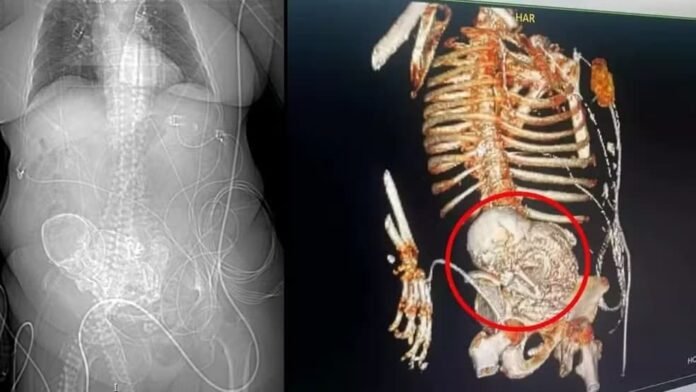

A mulher deu entrada no HR de Ponta Porã com um quadro de infecção grave em 14 de março deste ano. No mesmo dia, uma tomografia constatou o feto calcificado na região do abdômen da idosa.

A idosa deu entrada no HR de Ponta Porã no dia 14 de março. Para precisar o diagnóstico, uma tomografia 3D foi solicitada. O exame foi responsável por identificar o feto calcificado no abdômen da mulher, de acordo com as informações da secretaria de Saúde de Ponta Porã.